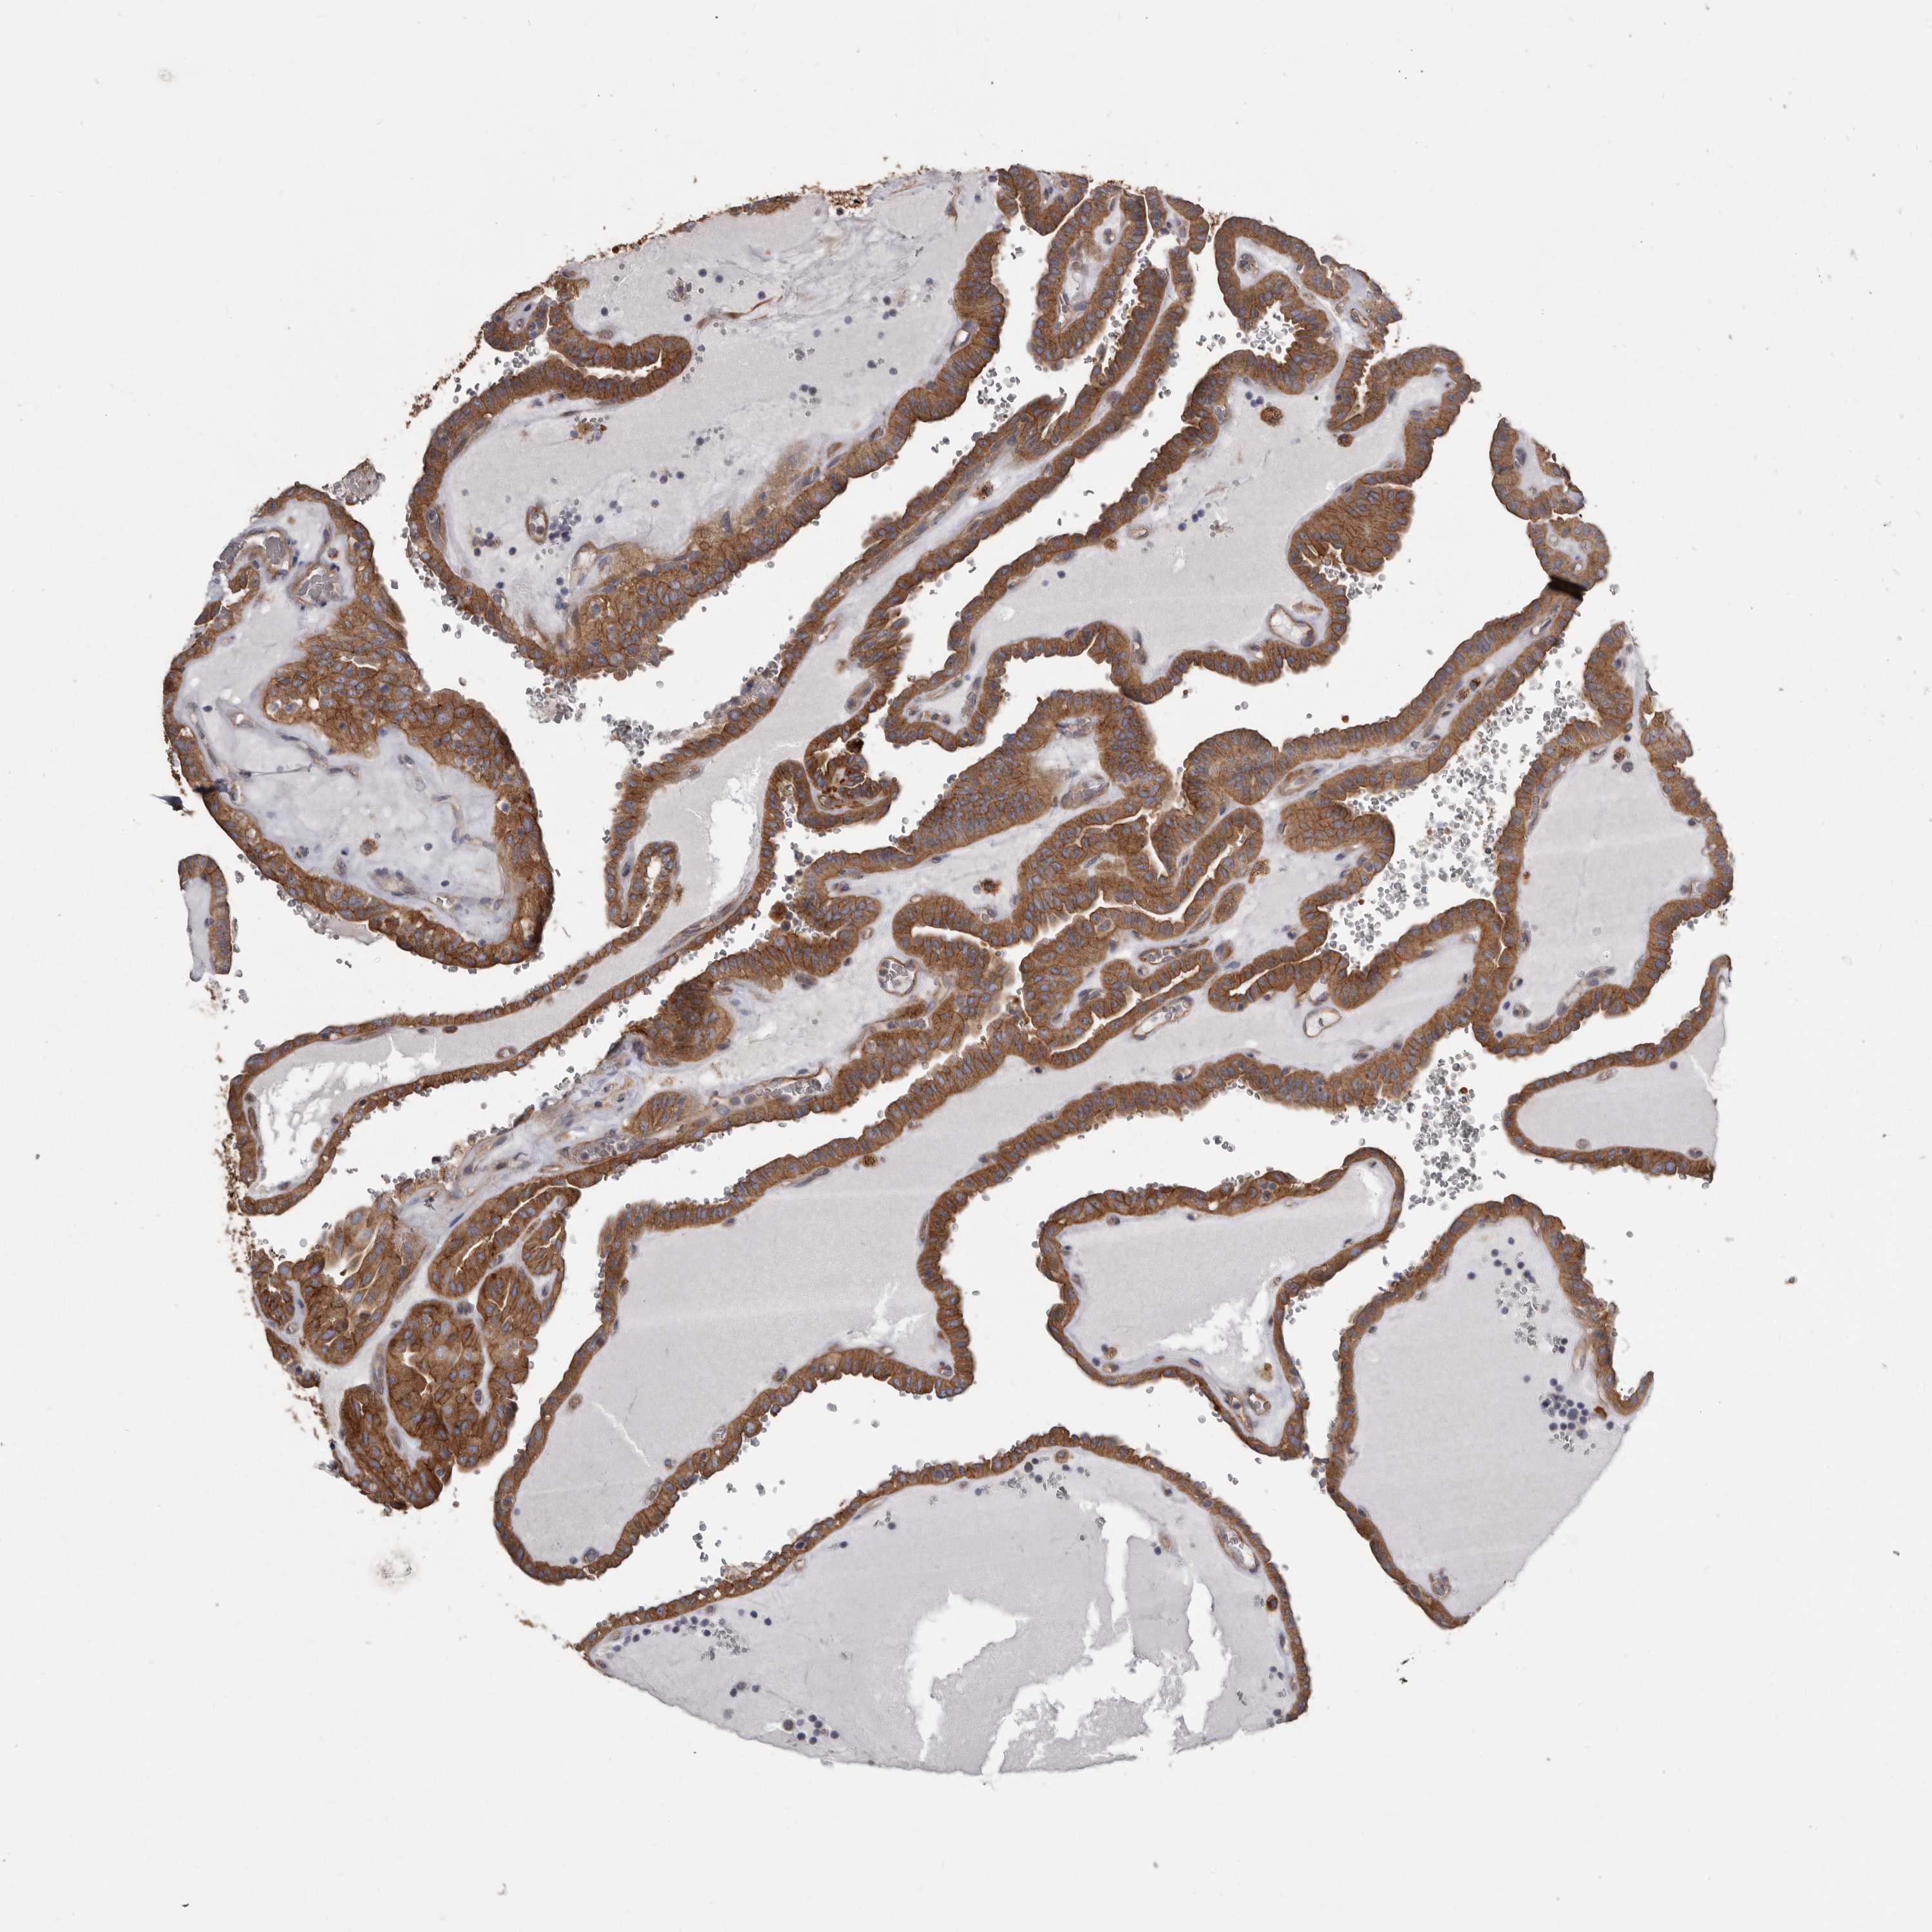

THYROID CANCER - Protein expressioni

A mouse-over function shows sample information and annotation data. Click on an image to view it in a full screen mode. Samples can be filtered based on level of antibody staining by selecting one or several of the following categories: high, medium, low and not detected. The assay and annotation is described here.

Note that samples used for immunohistochemistry by the Human Protein Atlas do not correspond to samples in the TCGA dataset.

Antibody stainingi

Antibody staining in the annotated cell types in the current human tissue is reported as not detected, low, medium, or high, based on conventional immunohistochemistry profiling in selected tissues. This score is based on the combination of the staining intensity and fraction of stained cells.

Each image is clickable and will lead to virtual microscopy that enables deeper exploration of all samples and also displays staining intensity scores, fraction scores and subcellular localization as well as patient and tissue information for each sample.

Antibody HPA028448

Antibody HPA028696

Staining

High

Medium

Low

Not detected

Intensity

Strong

Moderate

Weak

Negative

Quantity

>75%

75%-25%

<25%

None

Location

Nuclear

Cytoplasmic/membranous

Cytoplasmic/membranous,nuclear

Papillary adenocarcinoma, NOS

Follicular adenoma carcinoma, NOS